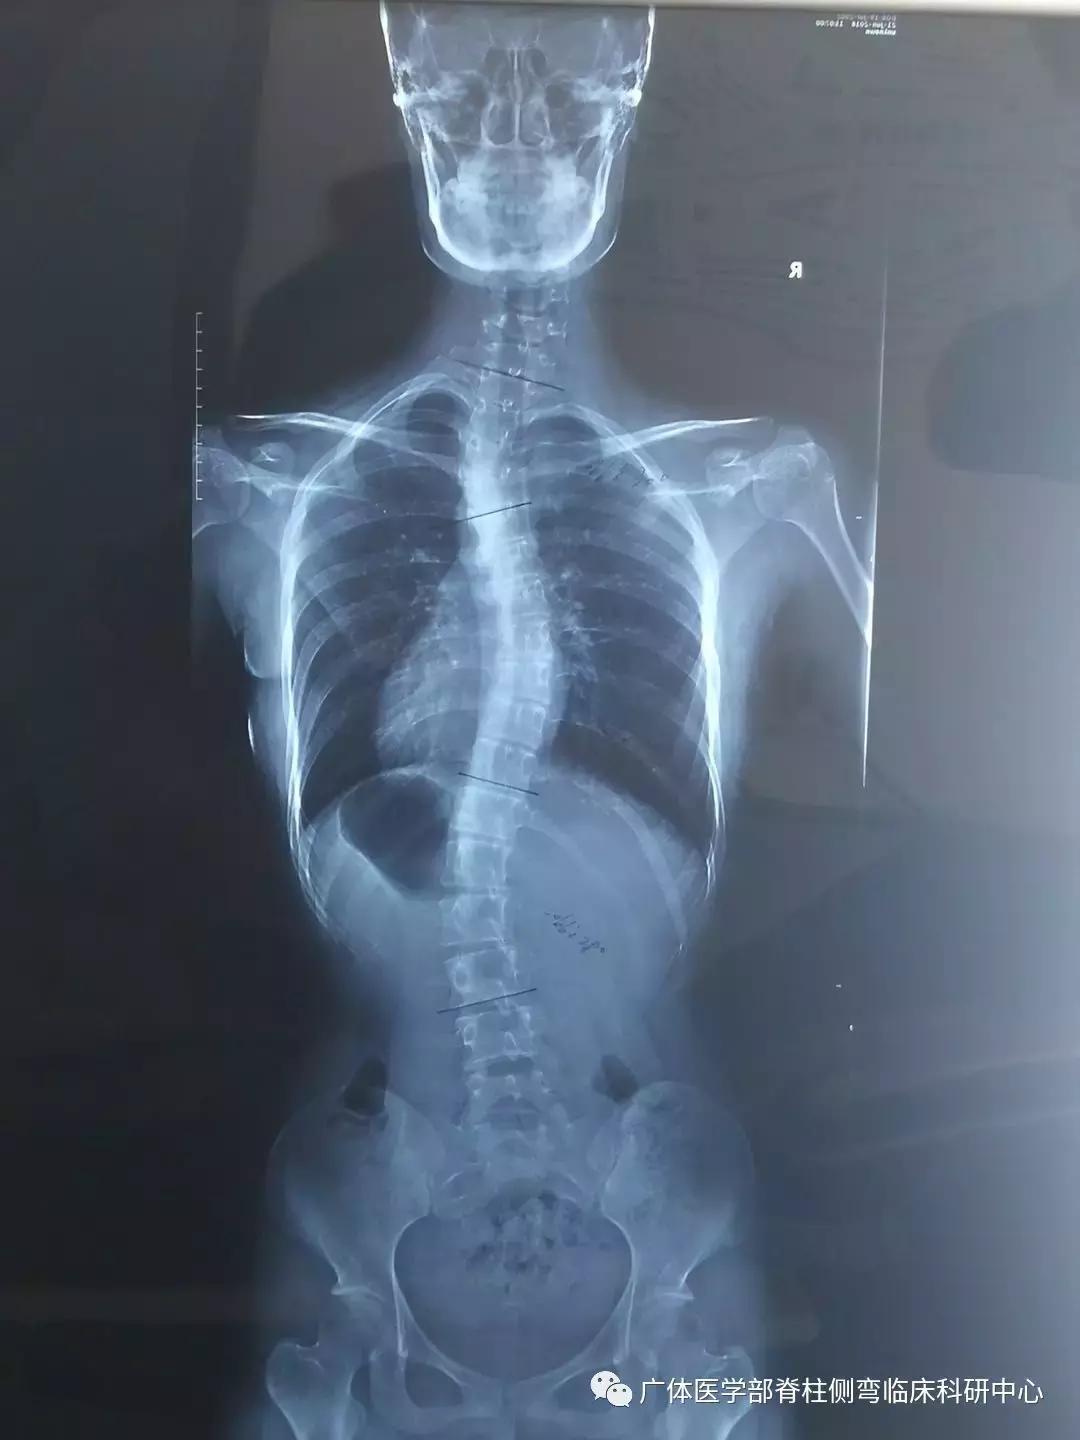

X片提示:RigoB1型(伴近胸弯),T1-T4左凸Cobb30°,T5-T11右凸Cobb29°;T11-L3左凸28°。